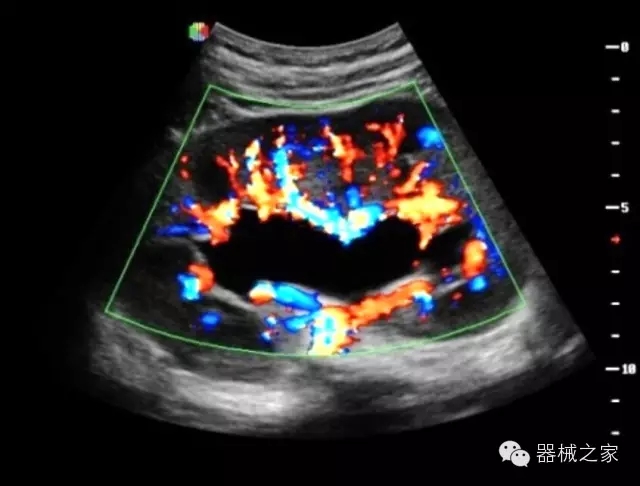

臨床圖片賞析

·智能微血流成像技術(shù):智能微血流捕捉技術(shù)可以提取出隱藏在背景噪聲中的弱血流信號(hào),大大提高低速血流的敏感性;

·移植S40高端臺(tái)式彩超高端平臺(tái)技術(shù),滿足超聲科腹部、淺表、婦產(chǎn)科、心血管、肌骨等應(yīng)用,提供超聲科完美解決方案;